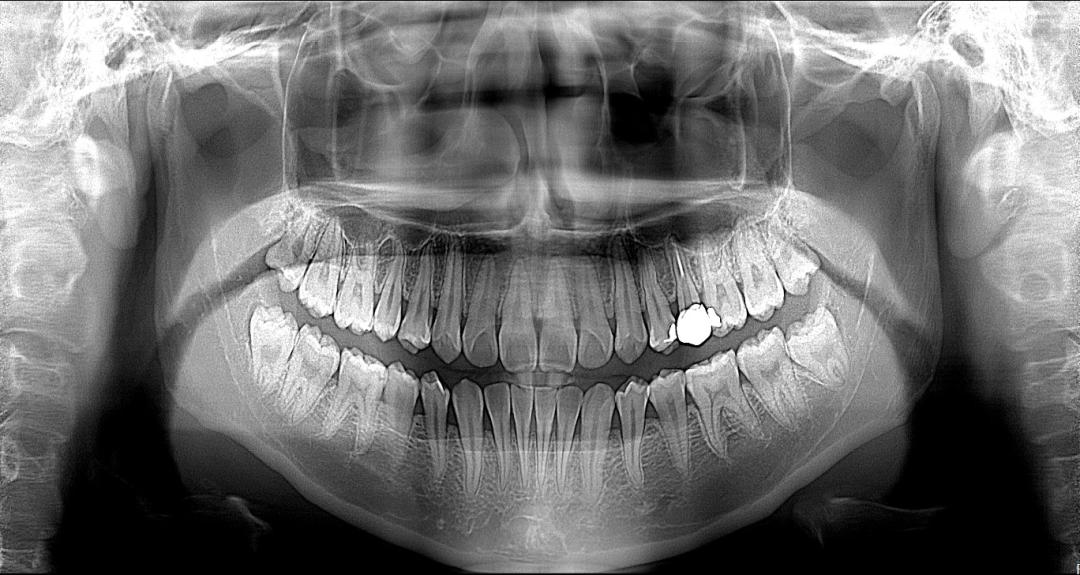

(图:伯爵3合1口腔CT全景片)

01 多聚焦全景,让摆位不再是难题

全景片由于其原理原因导致对患者拍摄摆位很高,一旦摆位不佳,易出现各种伪影,从而导致前牙不清晰,牙齿失真变形,组织重叠等。

伯爵3合1口腔CBCT采用多聚焦全景技术,一次生成5张全景片,兼容更多摆位不佳导致的影像问题, 上下前牙更清晰